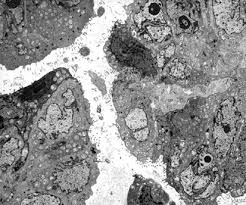

Conventional histology and electron microscopy revealed the tumor to be a malignant mesothelioma. Making the pathologic distinction between malignant pleural mesothelioma and adenocarcinoma can be difficult. We established primary mesothelioma cultures from pleural and ascitic fluids of five patients with advanced mesothelioma. electron microscopy often showed the presence of abundant long, slender microvilli on the cell membrane of the neoplastic cells. Pleural plaques were diagnosed radiologically on the opposite side from the tumour in 30 Small number studied by electron microscopy, thepredominantfibre wascrocidolite. (1) it was first described in 1985 by talerman et al. Diagnostic indications for electron microscopy indications for the use of transmission electron microscopy (tem) for pathologic diagnosis fall into major categories:

Conventional histology and electron microscopy revealed the tumor to be a malignant mesothelioma. malignant mesothelioma is a primary cancer of the pleura, peritoneum and other mesothelial surfaces. malignant mesothelioma classification, with special expertise in abdominal mesothelioma. Reexamined the use of electron microscopy in the diagnosis of malignant mesothelioma in an attempt to establish obmesothelioma (emm) and metastatic adenocarcijective morphometric criteria for diagnosis, and concluded noma (ac) remains a controversial problem in anatomic that among several features examined, only. Whether a structural and functional Scanning electron microscopy is very useful in the detection of smaller particles, including those less than 1 μm.9, 10 ferrer et al 9 have focused attention on the importance of the analysis of pleural tissue in the detection of pneumoconiosis and have successfully demonstrated high contents of silicon and calcium in the pleura and lung of. (1) it was first described in 1985 by talerman et al. malignant mesothelioma is a disease in which malignant (cancer) cells are found in the pleura (the thin layer of tissue that lines the chest cavity and covers the lungs) or the peritoneum (the thin layer of tissue that lines the abdomen and covers most of the organs in the abdomen). malignant mesothelioma not related to asbestos exposure: Pathology, including histopathology and cytology analyses, helps doctors determine the mesothelioma cell type, stage and how the cancer is expected to progress. Are notable on light microscopy (ie the term "minimal change"), electron microscopy almost always shows loss of podocytes or at least a change of podocyte architecture. electron microscopy and immunohistochemistry (ihc) confirmed their mesothelial origin. Primary malignant mesothelioma of the tunica vaginalis of the testis.

electron microscopy of two cases revealed a polymorphous population of fibrohistiocytic cells resembling those typical of malignant fibrous histiocytoma, admixed with lymphocytes and plasma cells, but sporadic cells expressed mesothelial properties in the form of sinuous villiform processes, intracytoplasmic neolumina lined by microvilli, and.

For this purpose, histochemical and immunohistochemical studies are needed. Immunohistochemistry, and occasionally electron microscopy, are required to support the histologic diagnosis. electron microscopy and immunohistochemistry (ihc) confirmed their mesothelial origin. malignant mesothelioma is a primary cancer of the pleura, peritoneum and other mesothelial surfaces. electron microscopy disclosed that the tumor cells contained prominent microvilli, basal laminae adjacent to the stroma, junctional complexes. electron microscopy of two cases revealed a polymorphous population of fibrohistiocytic cells resembling those typical of malignant fibrous histiocytoma, admixed with lymphocytes and plasma cells, but sporadic cells expressed mesothelial properties in the form of sinuous villiform processes, intracytoplasmic neolumina lined by microvilli, and. A case of peritoneal maligant mesothelioma in a radiation technologist, who had worked in this field for 34 years, is reported. malignant mesothelioma is a disease in which malignant (cancer) cells are found in the pleura (the thin layer of tissue that lines the chest cavity and covers the lungs) or the peritoneum (the thin layer of tissue that lines the abdomen and covers most of the organs in the abdomen). Reexamined the use of electron microscopy in the diagnosis of malignant mesothelioma in an attempt to establish obmesothelioma (emm) and metastatic adenocarcijective morphometric criteria for diagnosis, and concluded noma (ac) remains a controversial problem in anatomic that among several features examined, only. The development and evaluation of new therapeutic approaches for malignant mesothelioma has been sparse due, in part, to lack of suitable tumor models. (1) it was first described in 1985 by talerman et al. Eighty percent of all cases are pleural in origin. Immunohistochemical panels are integral to the diagnosis of mm, but the exact makeup of panels employed is dependent on the differential diagnosis.